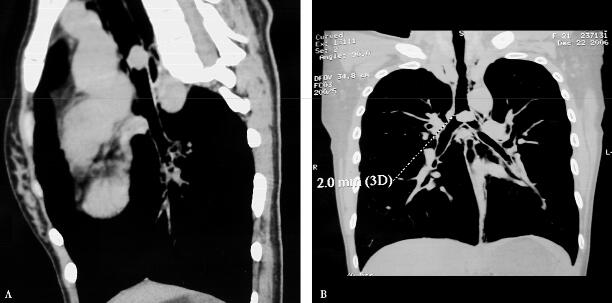

补充上述病史资料后,诊断思路逐渐清晰,患者气道内有阻塞因素,是异物附着在气管壁上?还是气管内肿物?需要进一步做胸部CT检查。胸部3D CT结果显示在隆突上方主气管内生长一肿物(图1A肺窗、B纵隔窗;图2A矢状位、B冠状位),左侧有蒂。因此解释了患者的临床症状特点,右侧卧位时,肿物下坠,将气管完全阻塞,造成患者窒息。左侧卧位时肿物与支气管右侧壁间留有缝隙,使呼吸困难稍有缓解。当气流通过狭窄的气管缝隙时产生哮鸣音,出现喘息症状。并随着肿物的增长,症状日趋严重。继而行纤维支气管镜检查,在隆突上方有圆形结节样肿物几乎将气管完全阻塞(图3),因肿物位置较高,未做活检,活检取材可能因创面出血导致窒息危及生命。

图2

图3